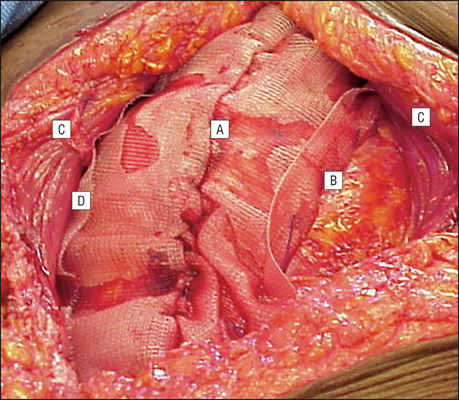

顱內血腫圖片

硬膜下血腫 (45)

硬膜下血腫 (46)

硬膜下血腫 (47)

硬膜下血腫 (48)

硬膜下血腫 (49)